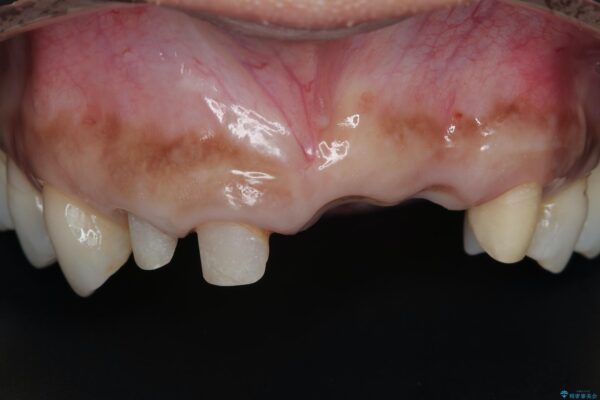

治療前

歯槽堤保存術を併用したブリッジ治療 治療前画像 歯槽堤保存術を併用したブリッジ治療 治療前画像 歯槽堤保存術を併用したブリッジ治療 治療前画像 歯槽堤保存術を併用したブリッジ治療 治療前画像 歯槽堤保存術を併用したブリッジ治療 治療前画像 歯槽堤保存術を併用したブリッジ治療 治療前画像 歯槽堤保存術を併用したブリッジ治療 治療前画像 歯槽堤保存術を併用したブリッジ治療 治療前画像 歯槽堤保存術を併用したブリッジ治療 治療前画像 歯槽堤保存術を併用したブリッジ治療 治療前画像